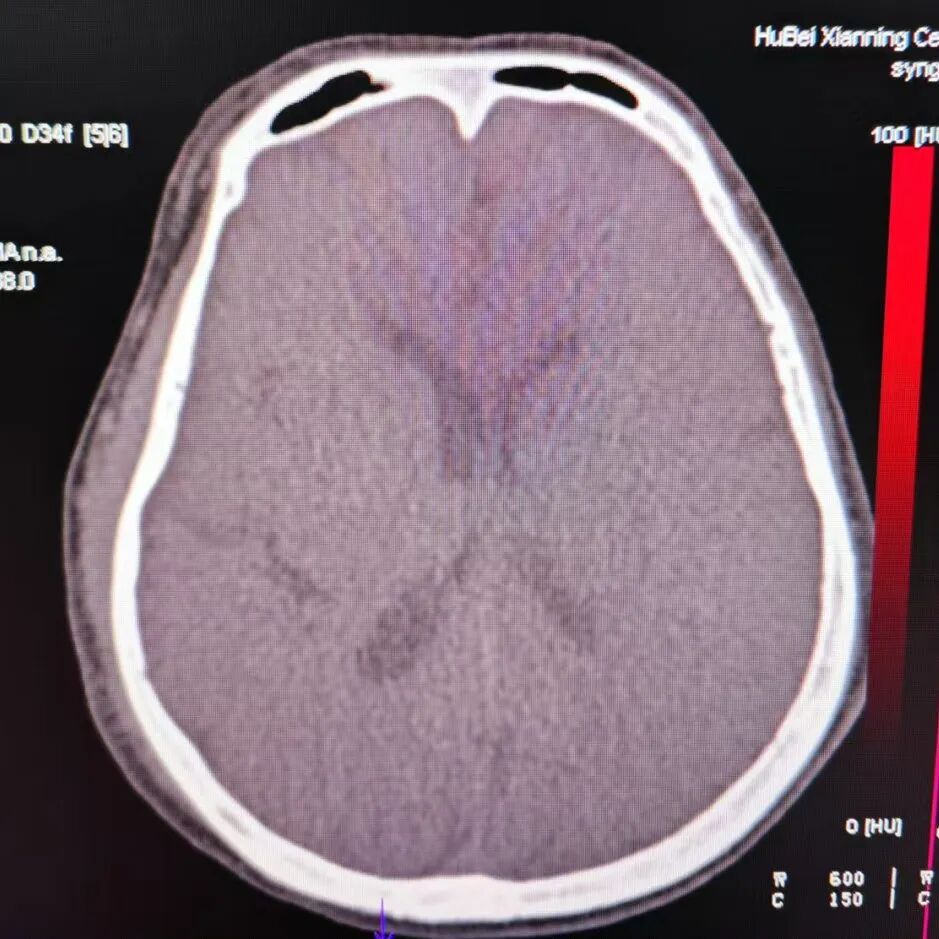

术后CT提示基底节区高密度灶。

动脉长鞘怎么置入有励可说|Locaste 088励楷长鞘及Tarvos微导丝在左侧大脑中动脉闭塞取栓术中的应用_https://www.jmylbn.com_新闻资讯_第22张

动脉长鞘怎么置入有励可说|Locaste 088励楷长鞘及Tarvos微导丝在左侧大脑中动脉闭塞取栓术中的应用_https://www.jmylbn.com_新闻资讯_第23张

去碘后考虑造影剂外渗。

动脉长鞘怎么置入有励可说|Locaste 088励楷长鞘及Tarvos微导丝在左侧大脑中动脉闭塞取栓术中的应用_https://www.jmylbn.com_新闻资讯_第24张

动脉长鞘怎么置入有励可说|Locaste 088励楷长鞘及Tarvos微导丝在左侧大脑中动脉闭塞取栓术中的应用_https://www.jmylbn.com_新闻资讯_第25张